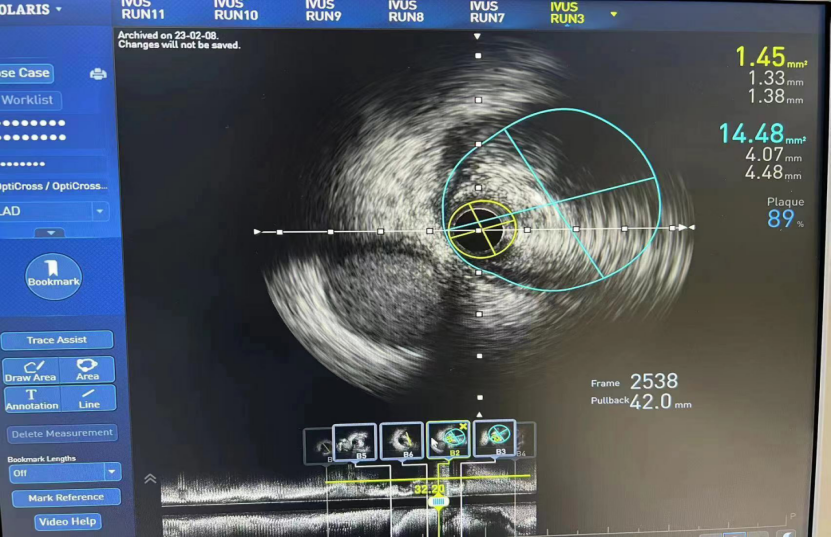

术前超声影像:

LM

MLA 最小管腔面积:2.15mm²

LAD

MLA 最小管腔面积:1.45mm²

LCX

MLA 最小管腔面积:2.43mm²

MSA 最小支架腔内面积 12.94mm²

MSA 最小支架腔内面积 7.0mm²

MSA 最小支架腔内面积 5.92mm²